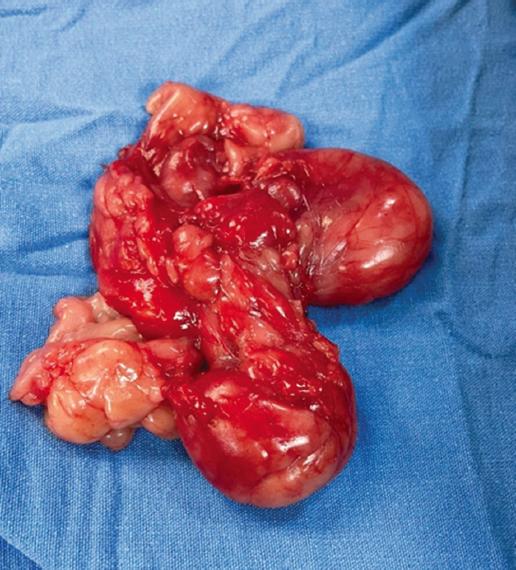

Se obtuvo un tumor lipomatoso completo (Fig. 5), dentro de su cápsula. Al final de la cirugía se optó por sutura con puntos simples con Vycril 3-0 desde planos profundos, dejando una única herida quirúrgica en la pared lateral izquierda del vestíbulo de la cavidad oral (Fig. 6).

Al poner en una balanza los riesgos y la seguridad de la cirugía junto a los términos estéticos, decidimos usar un abordaje intraoral. Al ampliar la incisión anteriormente y completar 4 cm de longitud se pudo ampliar la visualización del campo quirúrgico. La disección digital y roma con gasa nos ayudó a desprender el tumor logrando un campo quirúrgico limpio. Con esto se logró la resección completa de la tumoración, con su cápsula intacta (Fig. 6) y con óptimos resultados estéticos y ninguna complicación.